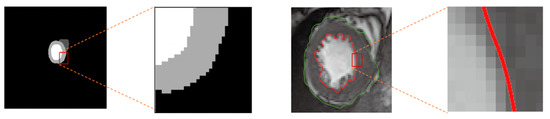

3.2. Shape Constraint Contour Evolution